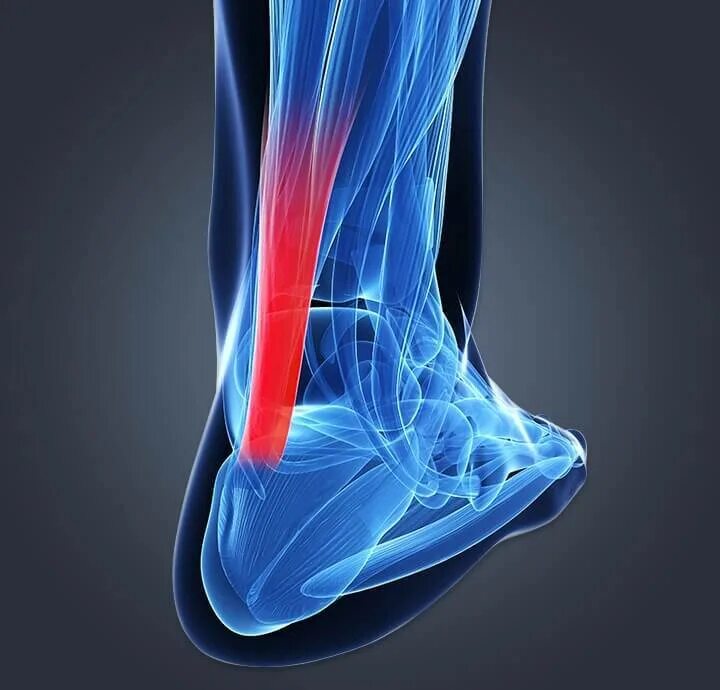

Ахиллобурсит мкб 10 у взрослых